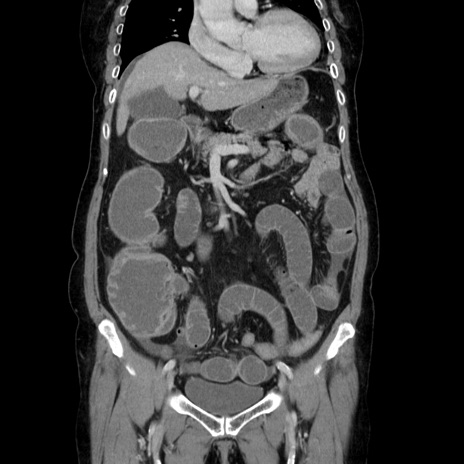

症例5(冠状断像)

【症例】70歳代女性

【主訴】お腹が張る

【現病歴】1週間くらい前から腹部膨満の自覚あり。昨日夜から増悪したため、本日救急外来受診。

【身体所見】意識清明、BT 36.5℃、BP 165/106mmHg、HR 80bpm、SpO2 98%、腹部:膨満、軟、自発痛・圧痛なし、触診にて不快感あり、腸蠕動音:減弱

【データ】WBC 12600、CRP 1.04